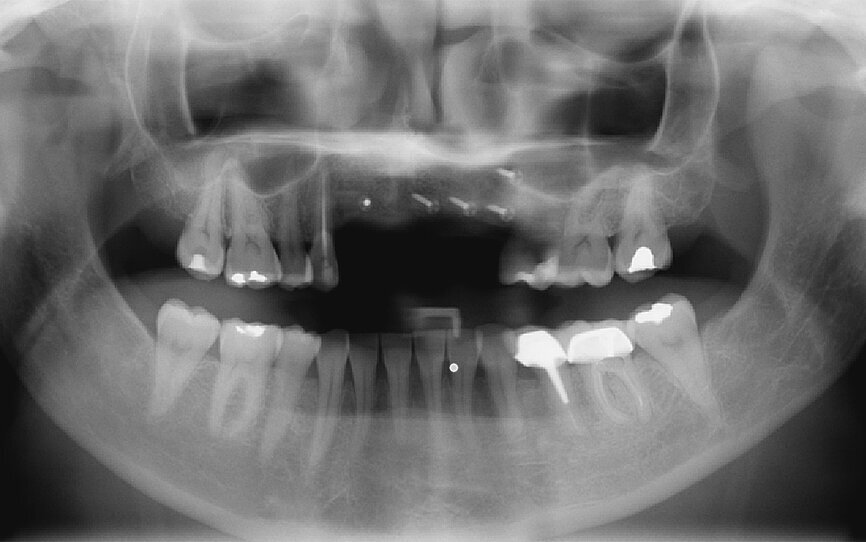

Fig. 10: Panoramic radiograph showing the grafts to be correctly healed and satisfactorily adhered to the recipient bone sites.

Fig. 40: Radiographic check-up after seven years.

Pre-implant prosthetic study

After four months, according to radiographic examination, the tissue had healed and the bone mass appeared stable (Fig. 10). New impressions were taken to prepare for the next step in treatment: the implant drilling guide. After four months of healing, the increased vestibular bone volume allowed positioning the teeth at the crestal bone and reduction of the false gingiva using additional wax (Fig. 11). A key of the added wax was taken and fabricated in clear casting resin. The implant positions were decided on and finalised by drilling placement holes, determining the exact position of the implants (Fig. 12). The correct positioning of implants in relation to the future prothesis is an important prerequisite for aesthetic and functional success.

Regular check-ups

Retreatment was regularly monitored with patient check-ups (Fig. 40). All implant treatments, no matter of what type, must be rigorously monitored in all treatment phases, but a retreatment requires even more diligence. A patient affected by the failure of a previous treatment will not accept even the smallest problem. To this end, the role of healing periods is thus essential to retreatment success.